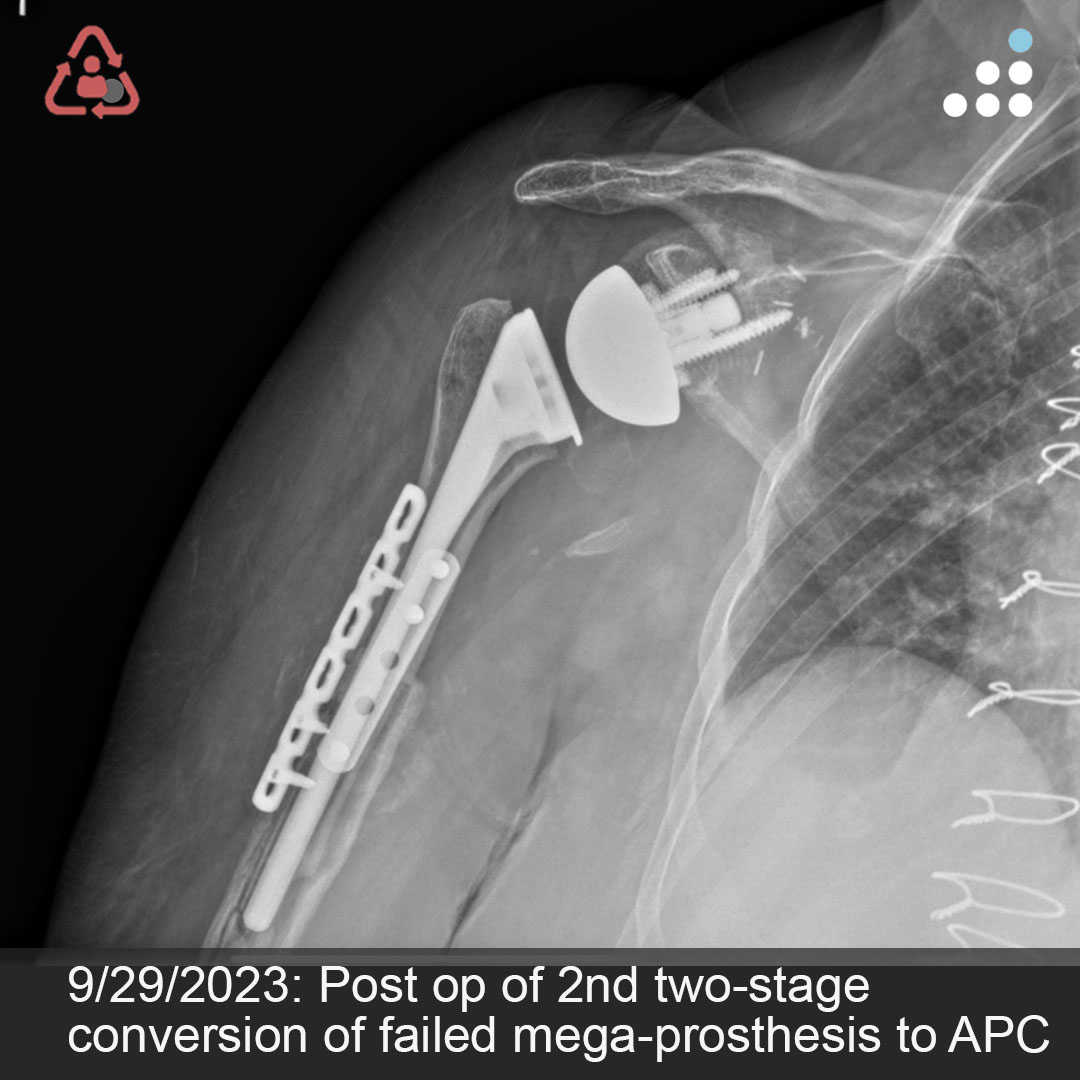

@orthobullets If there is still some cartilage left on the reverse Hill Sachs I’ve had some luck with doing a humeral head osteoplasty. I’ll use allograft chips or cement to backfill the defect after I tamp up articular surface and then try to get everything repaired especially in young pts